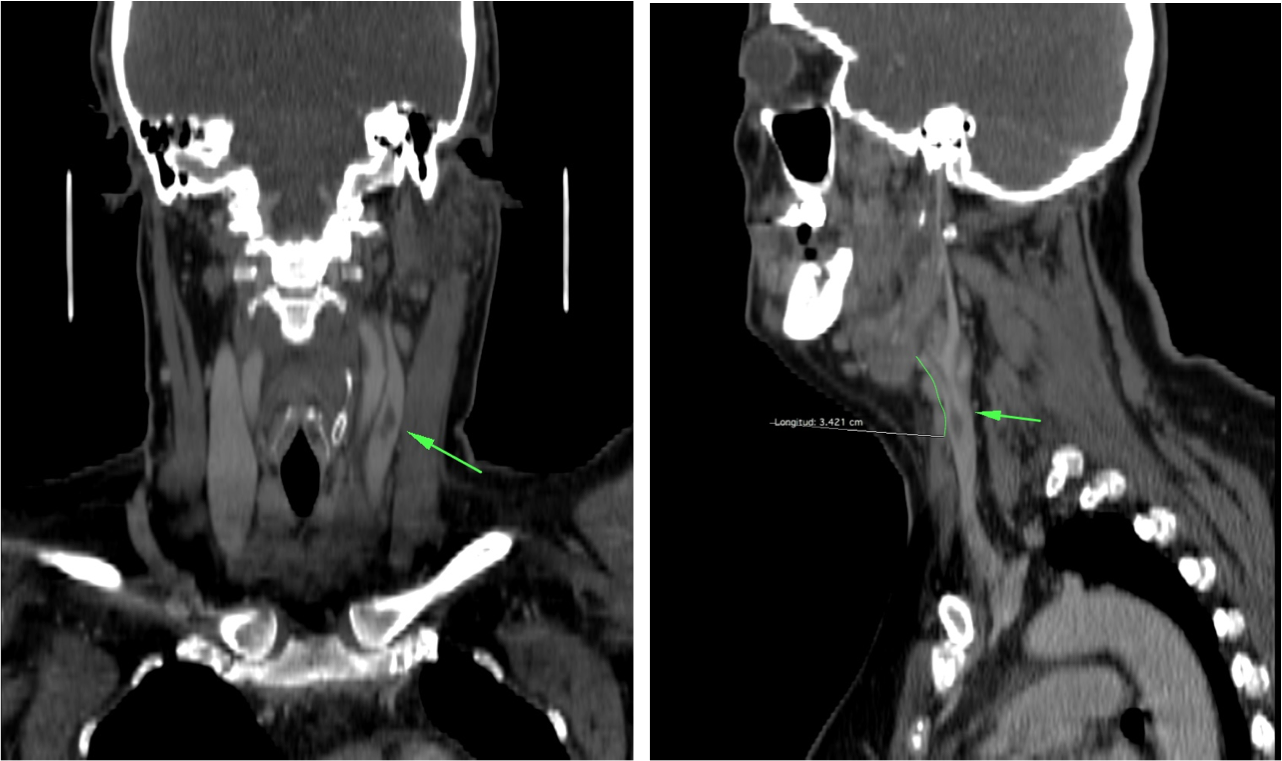

Síndrome de Lemierre: Tras una infección de la orofaringe, se produce tromboflebitis de vasos de cuello. Suelen ser infecciones asociadas con comobilidades tales como cirugía o radioterapia.

- Los defectos de repleción en la TC con contraste indican trombosis.

- La afectación de la grasa perivascular indica proceso inflamatorio.

- Si hay afectación de la vena yugular interna, existe alto riesgo de migración de émbolos sépticos a los pulmones. Por tanto, dada la gravedad, es fundamental realizar además una TC de tórax y es el radiólogo el que debe sugerir o establecer el diagnóstico de la enfermedad en un primer momento.

- La afectación de la arteria carótida puede ocasionar importantes consecuencias. Suelen ser infecciones asociadas con comobilidades tales como cirugía radioterapia de neoplasias en el cuello. Se puede producir la afectación de la vasa vasorum ocasionando necrosis mural, celulitis, abscesos o formación de seudoaneurismas y/o disecciones.

En el estudio del tórax (no se muestra) no se evidenciaron alteraciones.